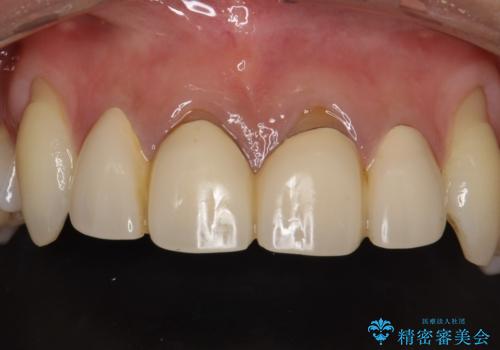

前歯の合計6本をオールセラミッククラウンにする計画としました。

一つ一つを独立したかぶせ物を装着することで、フロスも可能になり、清掃性が向上しました。